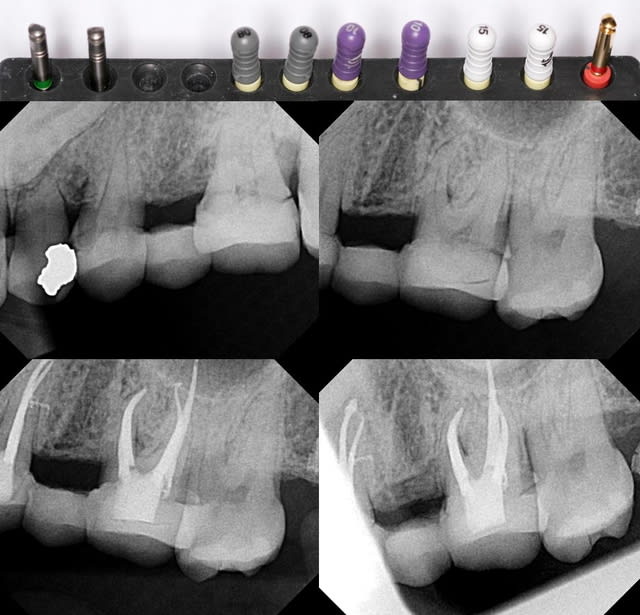

Cas clinique (par un collègue), il utilise sur la presque totalité de ses cas.

--

Céramik

Endo  f2  ghuutc - Eugenol

Un commenaire sur le cas de ton collègue :

1- je ne preconise pas les limes C+ pour explorer le canal ; ce sont des limes de retraitement; trop rigide ; mais c'est une reflexion personnelle.

2- il ne peut pas obtenir cette conicite canalaire avec le seul F2. Soit il traaille egalement avec les Gates de facon appuyée, soit il rajoute un instrument en coronaire (ce qui effectivement a beaucoup de sens). Mais la seule utilsiation du F2 ne permet pas cette mise en forme; notamment dans la partie coronaire.

Le cas est tres beau et repond aux objectifs que je me suis fixé personnellement.